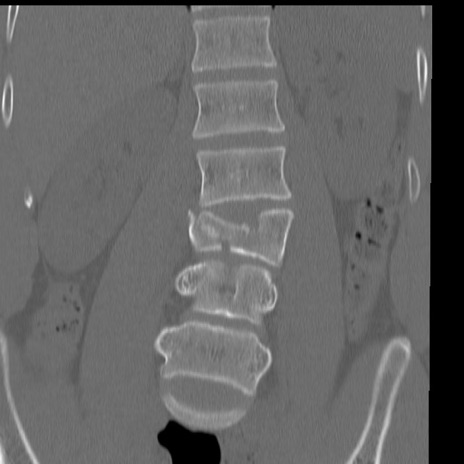

症例3 腰椎CT(冠状断像)

腰椎CT

矢状断像